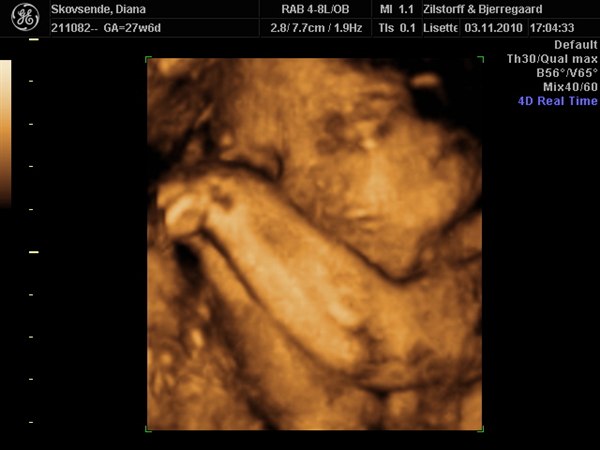

Idag har vi så været til 3D scanning og hun tjekket det hele og det så bare så fint ud de hele dog var min lille pige ikke særlig samarbejdsvillig så vi skal der ind igen på onsdag. Idag lå hun med hoved ned af og gemte sig bag sine finde hænder og vejer 948g så hun er en lille fin pige og hvis hun stadig vokser sådan kommer hun ud som en pige på 3200g det er jo fint Lucas kom ud som 3540g.

Ork ja det vi fik lov at se kunne vi. Helt sikkert min næse og nok også min mund men det var lidt svært fordi hun ikke var så samarbejdsvillig.

Lucas kunne vi se han havde fars næse og min mund og det passet også da han kom ud og det sjove ved det var at vi faktisk kunne kende ham fra 3D billederne af ham det var lidt vildt synes jeg. Så nu håber jeg vi kan få nogen rigtig ansigt billeder næste gang så vi rigtig kan se hende